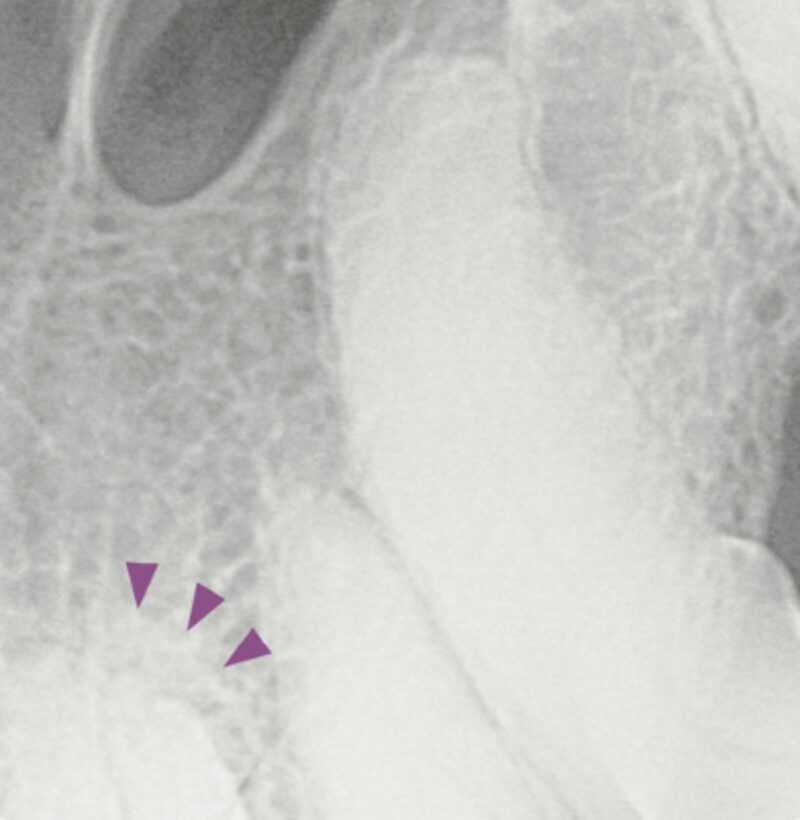

Der Röntgenbefund zeigt den doppelt angelegten I2 im Oberkiefer links sowie eine periapikale Radioluzenz (★) und einen erweiterten Parodontalspalt (▶️). Aufgrund der Überlagerung der Wurzelbereiche wie hier im linken Incisivibereich konnte dieser erst durch die Anfertigung einer intraoralen Schrägaufnahme besser beurteilt werden.

Differentialdiagnostisch sollten persistierende Incisivi – Milchzähne (▶️) ausgeschlossen werden. Sofern stomatologisch wie röntgenologisch keine Hinweise auf eine Zahnerkrankung vorliegen, kann der zusätzliche Zahn belassen werden. Allerdings wird ein Zuchtausschluss empfohlen.